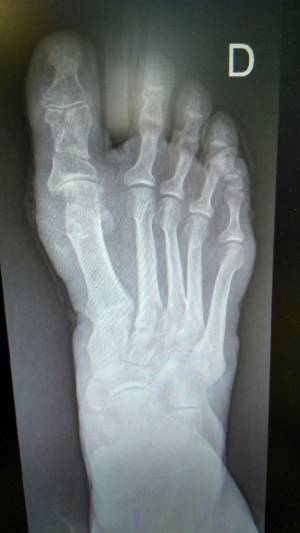

Estas deformidades son los llamados Hallux Valgus o popularmente conocidas como juanetes, que son deformidades que se generan en la parte externa del dedo gordo del pie cuando éste se desvía y comienza a apuntar hacia el segundo dedo. Es una afección que se vuelve dolorosa según evoluciona, y en cuya aparición influyen factores genéticos y posturales. Se puede prevenir utilizando calzados de horma ancha, pero cuando la afección es grave, finalmente la cirugía es la solución.

"Bajo anestesia local y una suave sedación se pueden realizar todas las correcciones que se requieran durante la cirugía. Hoy en día los equipos modernos como el fluroscan, nos proporcionan imágenes directas del pie sin tener que abrirlo y a través de pequeñas incisiones estratégicamente localizadas con un micro instrumental, vamos corrigiendo la deformidad utilizando un motor de revoluciones controladas con fresas especiales para quitar el sobre hueso; no colocamos ningún tornillo, ninguna aguja, ningún elemento de síntesis. El paciente sale caminando del quirófano por su propio pie con un zapato especial de suela de goma recta y velcro que utilizará durante un mes. A la semana de la intervención se retira el vendaje y los puntos de sutura, se coloca un vendaje de mantenimiento, de fácil colocación, que se cambia cada vez que el paciente lo demande por su higiene, reanudando una vida activa en forma progresiva, alternando con periodos de reposo", explica el Dr. Lipnizky.

Al mes de este procedimiento ambulatorio, se realiza un control aportando una radiografía y acorde a la evolución, se retira el zapato rígido para comenzar a calzarse uno convencional y se indica un plan de ejercicio de recuperación funcional.